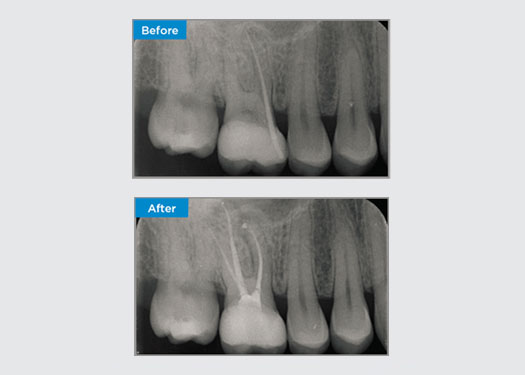

Casos clínicos

Los médicos de todas partes de Australia y Nueva Zelanda comparten amablemente presentaciones relevantes, interesantes y, a veces, desafiantes para los pacientes, junto con su selección de materiales y métodos para optimizar los resultados de sus pacientes.

En Dentsply Sirona, cada día destacamos a profesionales dentales de todo el mundo para que brinden a millones de pacientes un mejor cuidado dental y hagan sonreír a las personas. Nuestro enfoque de caso clínico se trata de compartir estas sonrisas, que los médicos de Australia y Nueva Zelanda han creado, con la comunidad dental en general.